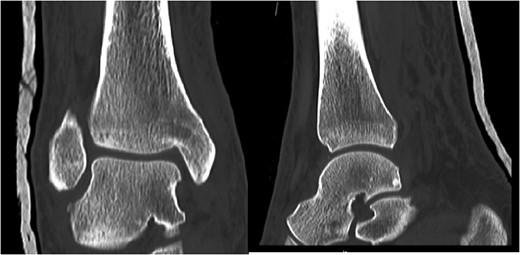

A 30-year-old male patient presented to Emergency Department (ED) following a run over injury. The patient described the mechanism of injury as moving his body over his run over foot. On clinical examination, there was obvious deformity and swelling of the right ankle. Dorsalis pedis pulse was felt but weak compared to the contralateral side with a capillary refill time under 3 s. The posterior tibial artery could not be palpated because of the deformity. X-rays showed posterior ankle dislocation without associated fractures (Fig. 1). Urgent reduction of the dislocation was done under sedation in ED. The knee was first flexed to relax the tendon Achilles then longitudinal traction with gentle forward force applied to the heel with immediate reduction of the deformity achieved. The foot was reassessed for vascular status. Triphasic pulse in both drosalis pedis and posterior tibial artery was detected with hand held Doppler. Ankle was immobilized in posterior below knee back slab to accommodate for swelling and check x-rays confirmed reduction of the ankle joint (Fig. 2). CT scan was done afterwards to define any subtle incongruity or osteochondral fragments entrapped in the joint. CT did not show any associated fractures and showed congruent reduction of the ankle joint (Fig. 3). Patient was mobilized touch weight bearing for first 2 weeks. The back slab was changed for weight bearing short leg cast and progressive weight bearing was allowed for the following 4 weeks. At 6 weeks follow up, plaster was removed and on examination patient still had moderate tenderness over the medial joint line and deltoid ligament area. Also, patient had limited range of plantar and dorsal flexion. Referral for physiotherapy was done for start of functional rehabilitation and range of motion exercises and in mean time MRI was done to delineate extent of ligamentous injury. MRI showed bone bruising of the lateral malleolus, medial malleolus and lateral talus (Fig. 4). The anterior talufibular ligament (ATFL), calcaneofibular ligament (CFL), posterior talofibular ligament (PTFL) and deltoid ligaments were sprained but intact. At 12 weeks follow up, patient could walk normally without any symptoms of instability and achieved 20° of both plantar and dorsal flexion. At 16 weeks, patient achieved full range of motion of ankle and was able to return to work. At 24 weeks follow up patient was able to resume his sport activates as preinjury level.

Plain film X-rays of right ankle showing total posterior dislocation of the ankle joint with no fracture of the medial or lateral malleolus.